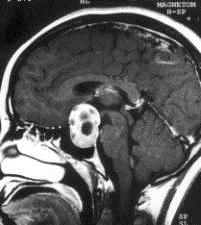

问题 病历摘要:??患者男性,35岁。性功能减退2年,视力下降6月。既往体健。体检:神清,皮肤细腻,毛发稀疏。视力左眼0.3,右眼0.5,双瞳等大等圆,直径3.5mm,对光反射稍迟钝,双颞侧偏盲,双眼底视神经乳头原发性萎缩,余神经系统未见异常。 关于鞍区周围的神经血管间隙的叙述哪些是正确的?